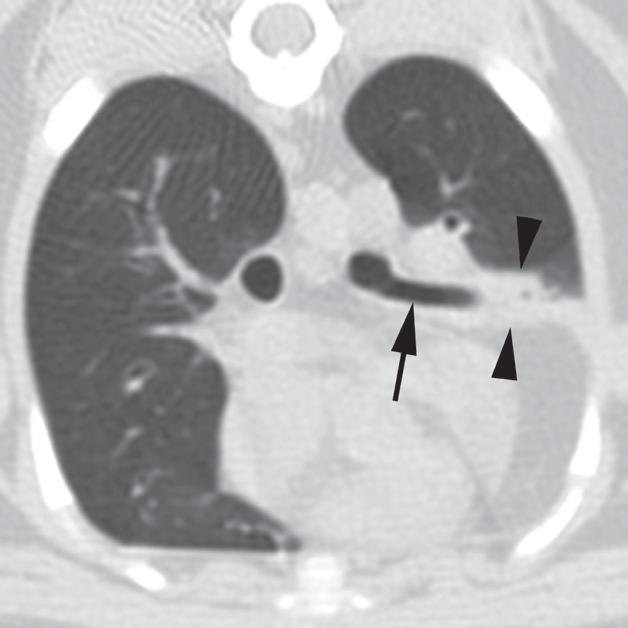

Rycina 4.6.1. Niedodma płata płuc (kot)

Badanie wykonano u 4-letniego, kastrowanego samca kota abisyńskiego z przewlekłą chorobą układu oddechowego. Obrazy na ryc. a i b są reprezentatywnymi skolimowanymi co 1 mm skanami poprzecznymi środkowej części klatki piersiowej wykonanymi na poziomie oskrzela płatowego lewego płata doczaszkowego (a) i prawego środkowego płuc (b). Obraz na ryc. c jest skośnym obrazem zrekonstruowanym w osi długiej, ukazującym prawy płat środkowy płuc. Lewe doczaszkowe oskrzele płatowe jest wypełnione powietrzem i ma prawidłowe położenie (a – strzałka), jednak płat płuca ma zmniejszoną objętość i zwiększoną atenuację z powodu niedodmy (a – groty strzałek). Podobne zmiany zaobserwowano w przypadku oskrzela płata prawego pośrodkowego płuc (b, c – strzałki) i płuca (b, c – groty strzałek). Obraz skośny wyraźnie ukazuje przebieg oskrzela prawego pośrodkowego płata płuc (c – strzałka). Pośrednia atenuacja okalająca niedodmowy prawy pośrodkowy płat płuca to tłuszcz opłucnowy/osierdziowy. W tym przypadku niedodma wielopłatowa rozwinęła się wtórnie do przewlekłego zapalenia płuc. Posiewy z wydzieliny oskrzelowej potwierdziły rozpoznanie zapalenia płuc wywołanego przez Mycoplasma pneumoniae